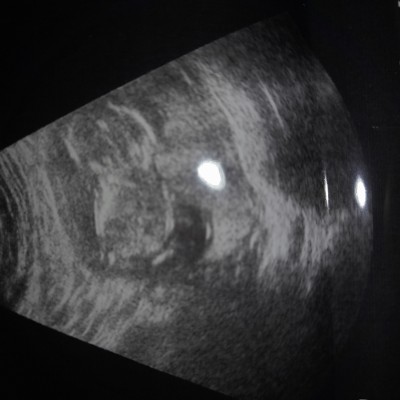

Yuzde 70 erkek denildi

cinsiyet tahmini alabilirmiyim

Gebelik haftası

14

%70 erkek ☺️